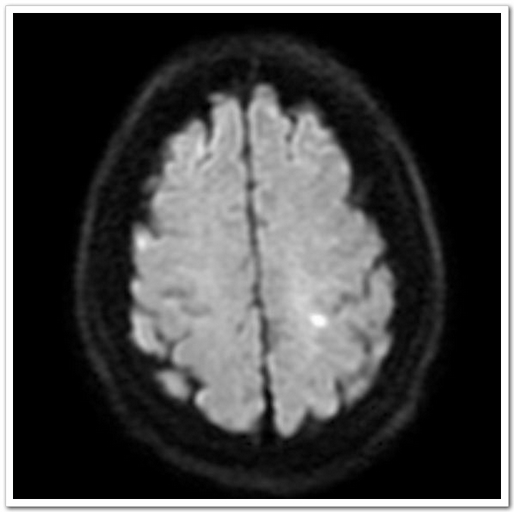

60歲的張阿姨這天正在家中看電視,突然感覺(jué)自己右側(cè)上肢使不上勁,主要為右手拿不穩(wěn)東西,日常生活動(dòng)作突然不能像平時(shí)那樣完成。真是人在家中坐,病從天上落,癥狀持續(xù)無(wú)明顯緩解,也無(wú)進(jìn)一步加重,遂至深圳大學(xué)總醫(yī)院神經(jīng)內(nèi)科就診。入院后頭顱CT排除腦出血;顱腦磁共振平掃M(jìn)RI+MRA:1.左側(cè)頂葉皮層急性腔隙性梗死灶。2.雙側(cè)額、頂葉皮層下少許缺血灶。3.頭顱MRA未見(jiàn)血管異常。

圖1:MRI:左側(cè)頂葉皮層急性腔隙性梗死灶